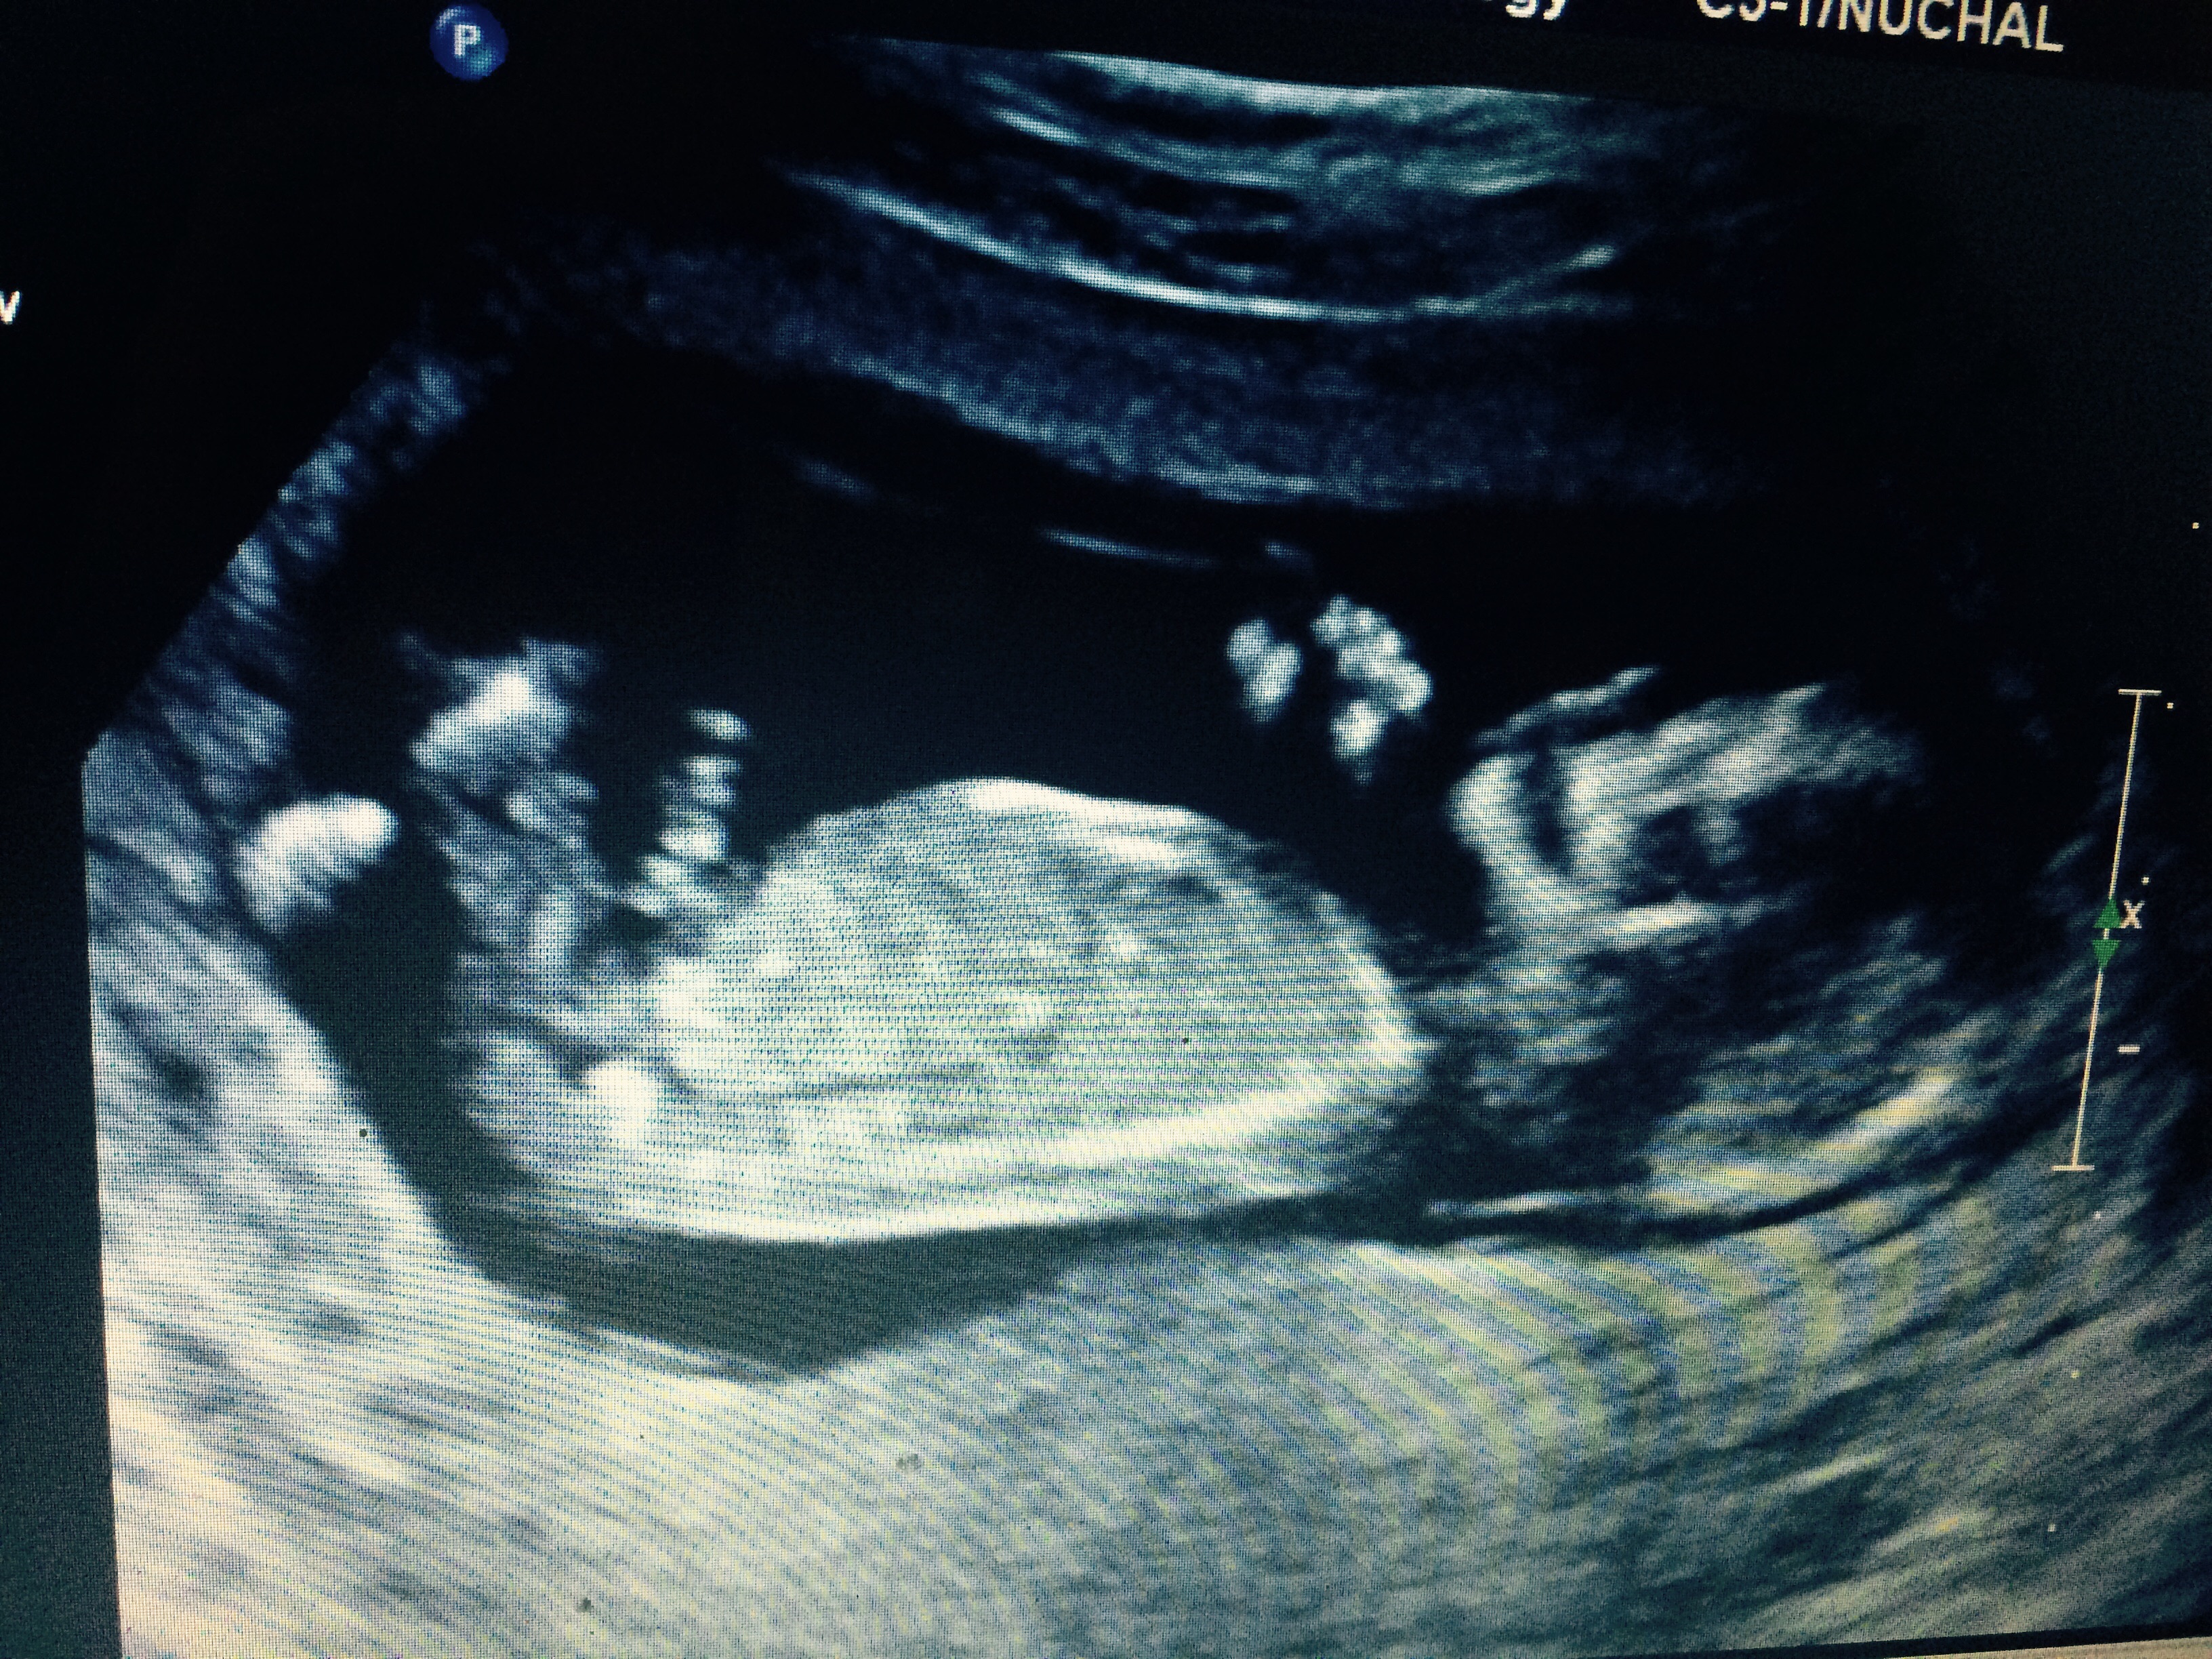

This was my 12.4 week ultrasound Attachment 22544

First scan sonographer said girl, last one they said boy. I have another to check progress just after 15 weeks so will update then :)

I agree with your sonos lol. 12.4 looks girly but I'm leaning boy on these 13.5 week ones though it's a bit messy down there with the cord and everything. I'm intrigued now! Good luck :). Hope your results all come back clear soon and you can stop worrying.